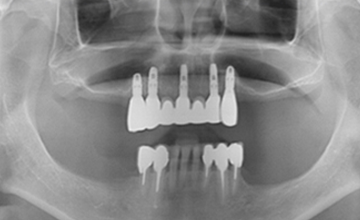

2개에서 4개 정도의 임플란트를 심고,

그 위에 딱 맞게 고정되는 틀니를 끼우는 방식입니다.

틀니 안쪽에 작은 고정장치가 있어

단추처럼 임플란트에 ‘딸깍’하고 끼워지는 구조라

일반 틀니보다 훨씬 덜 흔들리고 안정감이 좋습니다.